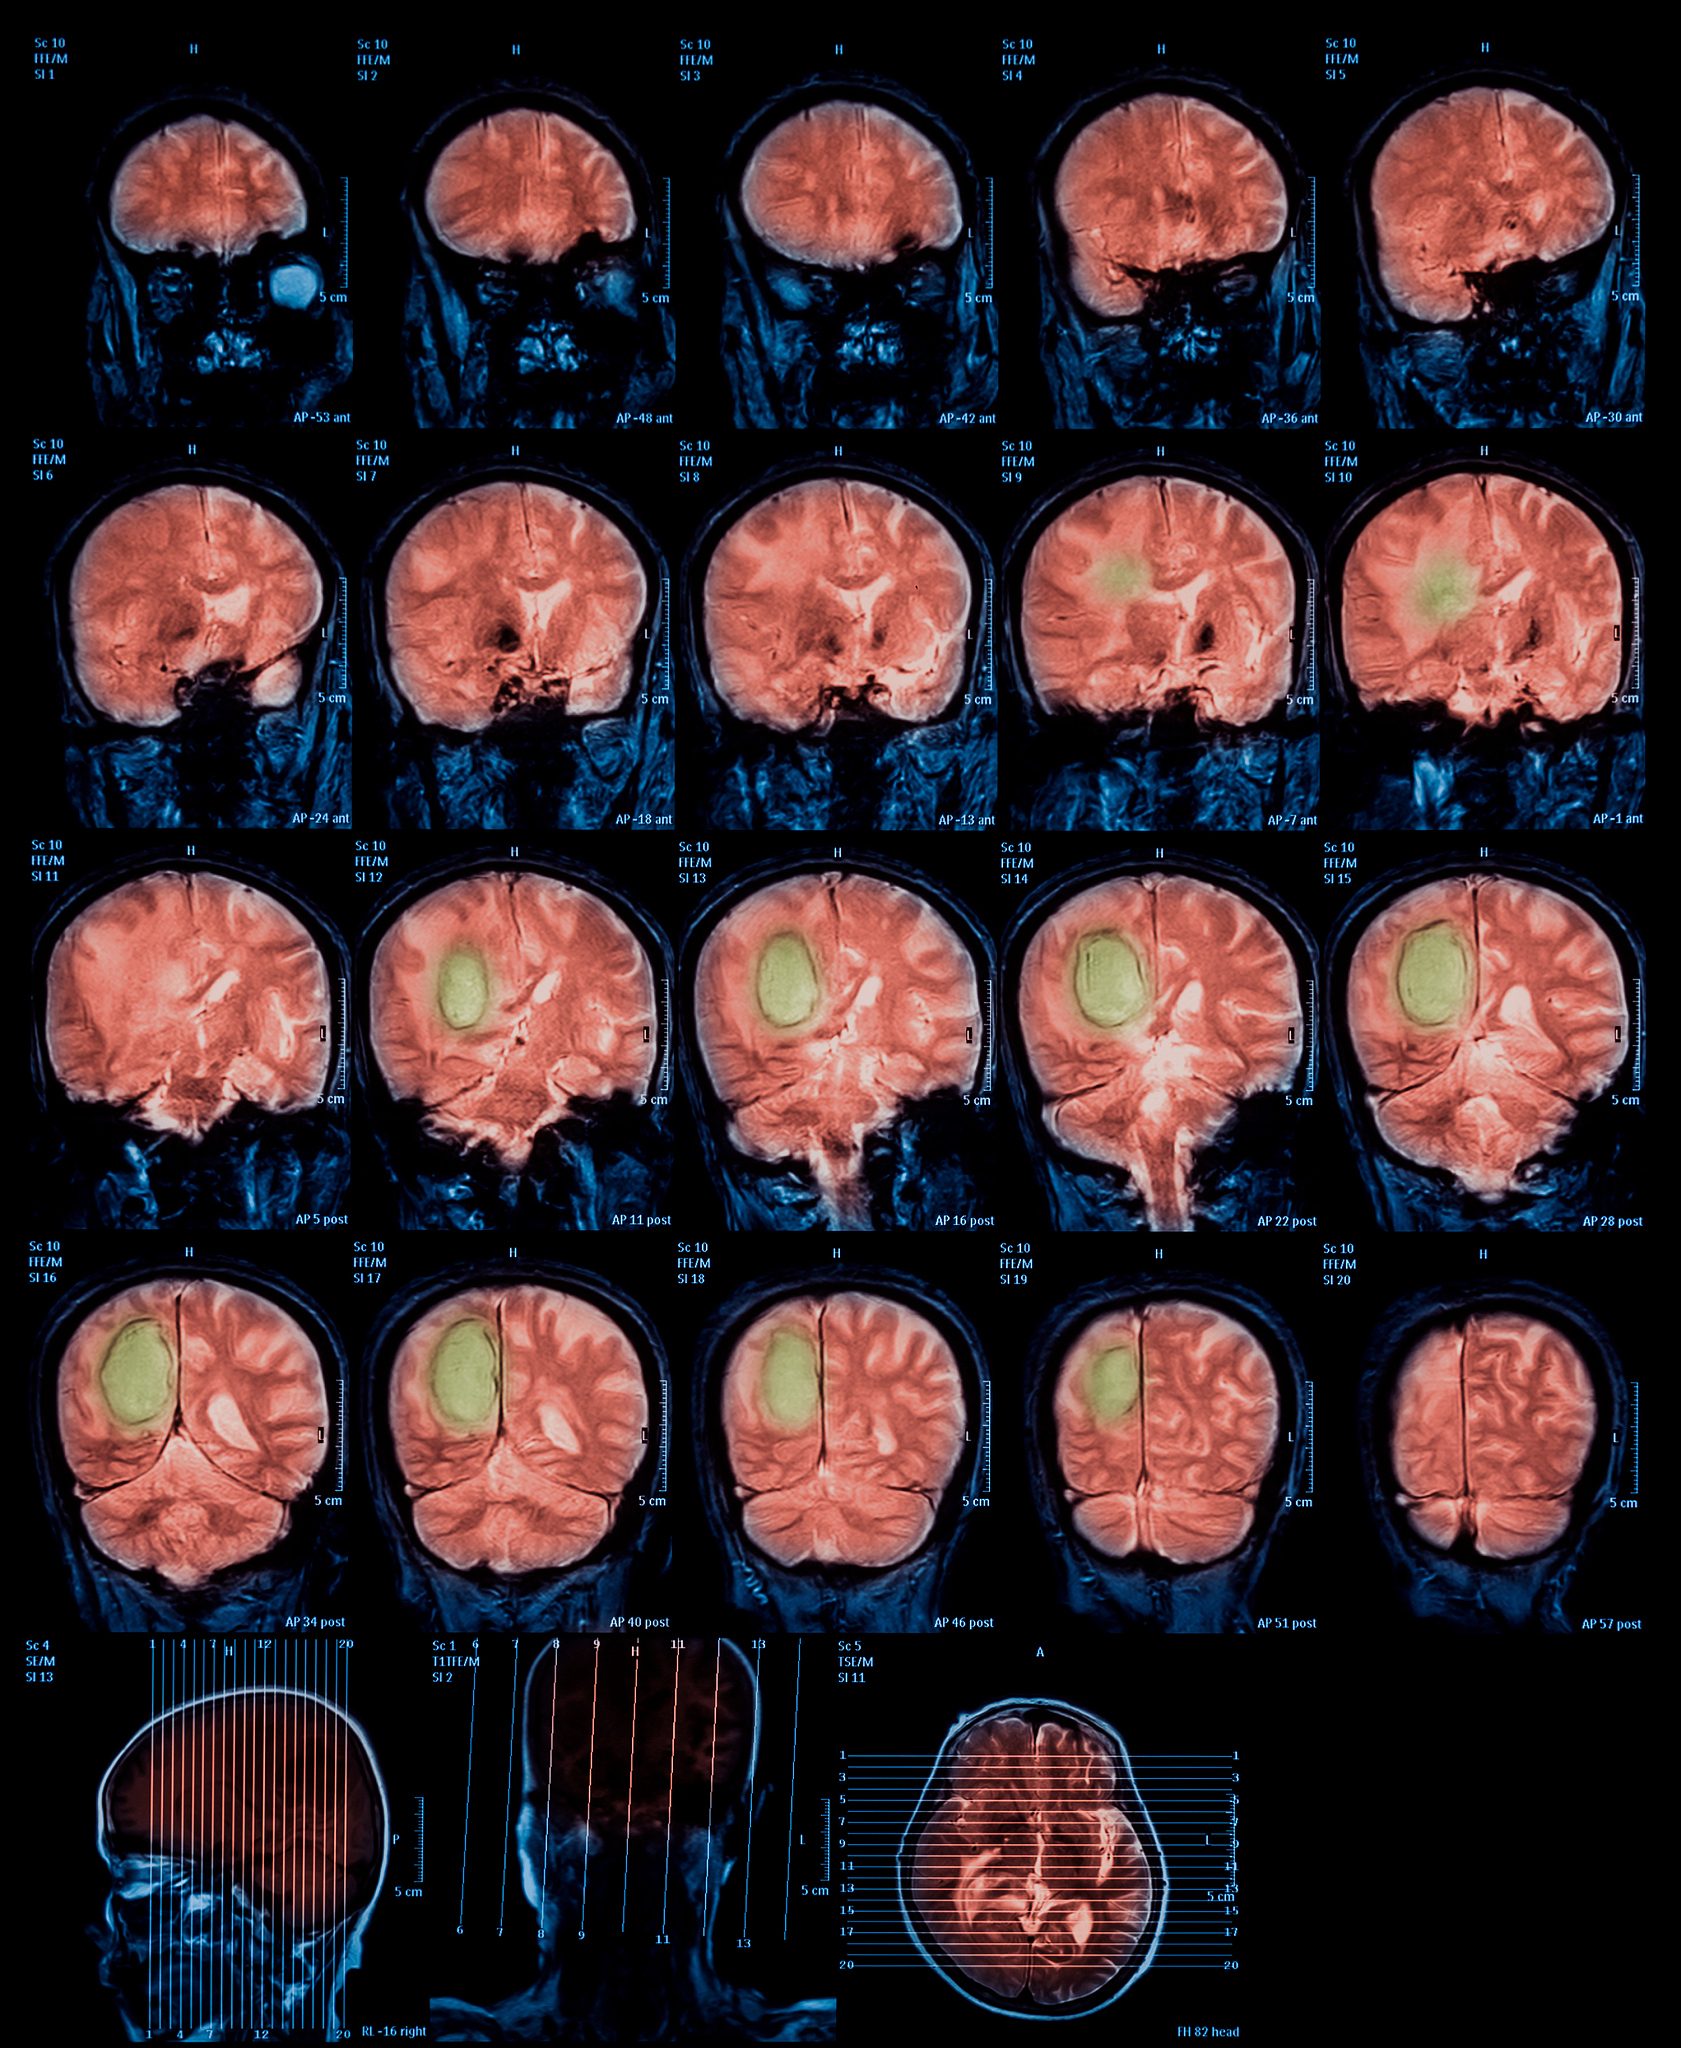

脑肿瘤是指在脑组织内形成的异常生长的肿瘤。它是由于脑细胞或神经系统中其他类型的细胞异常增殖而引起的。脑肿瘤可分为原发性脑肿瘤和转移性脑肿瘤两种类型。\n\n原发性脑肿瘤是指起源于脑组织内的肿瘤,通常分为良性和恶性两种。良性脑肿瘤生长缓慢,一般不会扩散到其他部位,但可能会对周围的脑组织造成压迫和损害。恶性脑肿瘤通常生长较快且具有侵袭性,可以扩散到其他部位,对脑组织造成更严重的损害。\n\n转移性脑肿瘤是指来源于身体其他部位的恶性肿瘤,如肺癌、乳腺癌、结肠癌等,经过血液或淋巴系统传播到脑部形成的肿瘤。\n\n脑肿瘤的症状因肿瘤的位置、大小和类型而有所不同,常见症状包括头痛、呕吐、癫痫发作、认知和记忆问题、肌力减退、感觉异常等。诊断脑肿瘤通常需要进行神经影像学检查,如MRI或CT扫描,并可能需要进行脑组织活检确认肿瘤类型。\n\n治疗脑肿瘤的方法包括手术切除、放疗和化疗等,具体治疗方案会根据肿瘤的类型、大小和患者的整体情况而定。脑肿瘤的预后取决于肿瘤的类型、分级、治疗的及时性以及患者的整体健康状况。